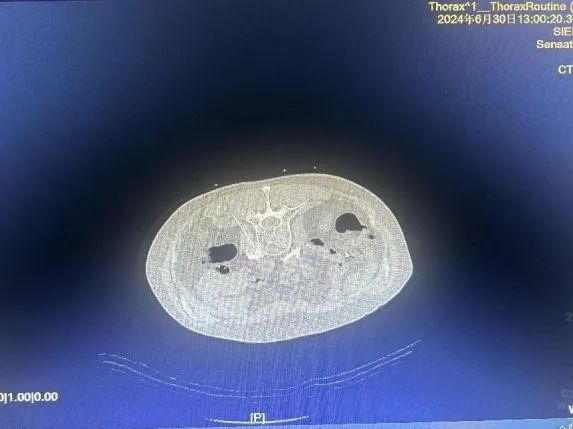

经诊断治疗,患者症状的显著改善,为整个诊疗团队实施进一步诊疗方案增添了信心,也给患者家属带来了希望。后经充分评估,在 CT 引导下为患者进行腰交感神经射频消融及药物毁损术。